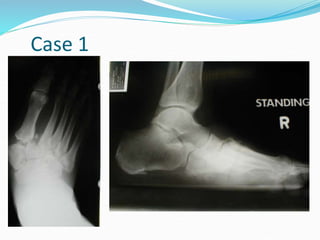

Case 1